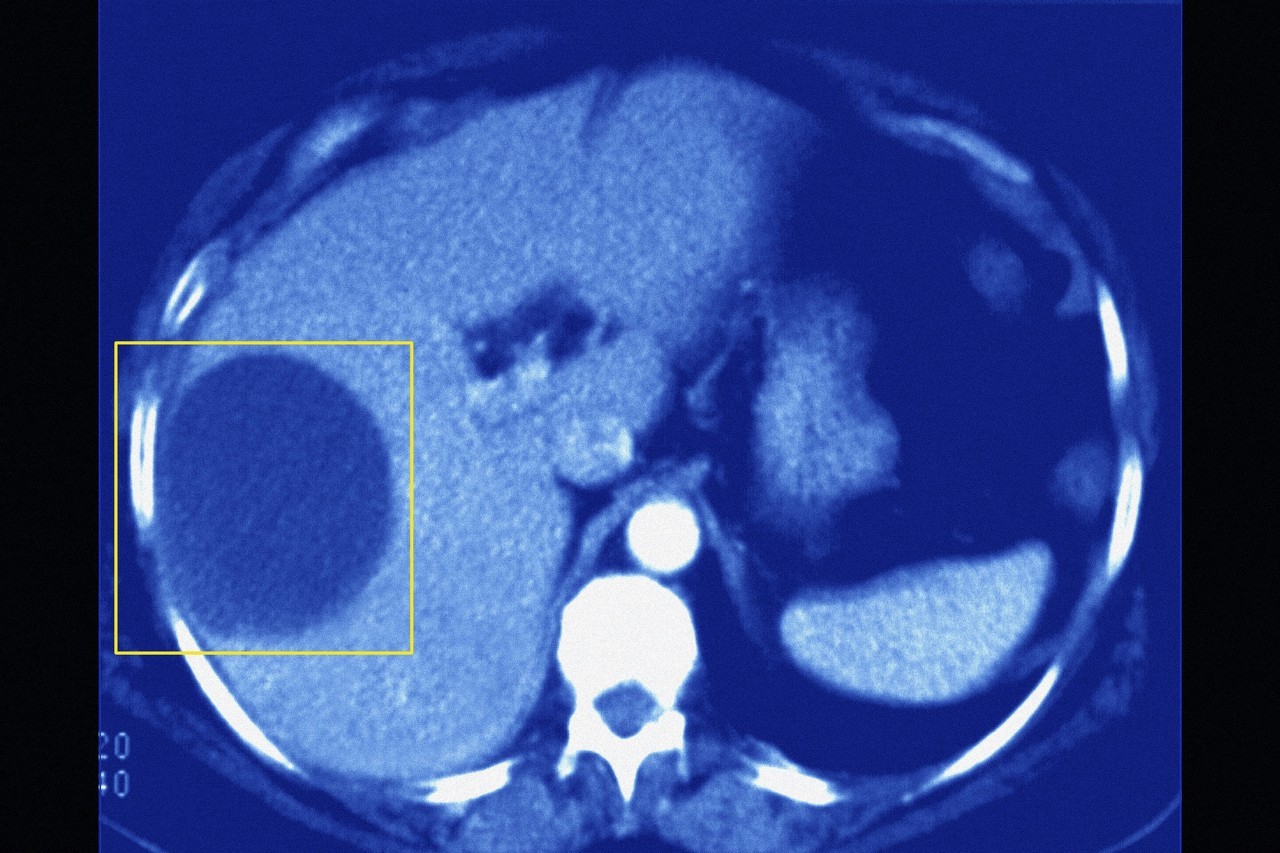

首先门诊上经常病人拿了CT片子给我们阅读,肝囊肿诊断已经明确,咨询外科医生是否需要手术,比较关心手术方案以及预后情况,下面我们谈一谈。

理想的肝囊肿治疗,腹腔镜肝囊肿去顶开窗引流手术。大家从这个名称不难发现,手术途径通过微创的方法。手术的治疗基础,是把突出肝脏的囊肿顶端部分囊壁祛除,就像一个“茶壶”把盖子去掉,把茶壶里的“囊液"引流到腹腔,再给予吸收。有患者会问,那"茶壶怎么办,"茶壶"就是生长在肝脏里面的囊肿壁,这部分囊壁是不处理的。那就有病友来问,“茶壶盖子”越大是否手术后效果越好?对的,开口大了囊液容易流出,腹腔内吸收。但是又有个问题,如果“茶壶盖”向上,那么站立的时候囊液不容易流出,并且与膈肌组织粘连,又形成新的“茶壶盖"。所以在临床上,经常有病人手术后开开心心,但是时间不久,很扫兴的来讲又复发了。

四,如果肝囊肿大但是完全长在肝脏深部,突出肝组织的囊壁非常小,这样手术开窗也小,不利于囊液引流。